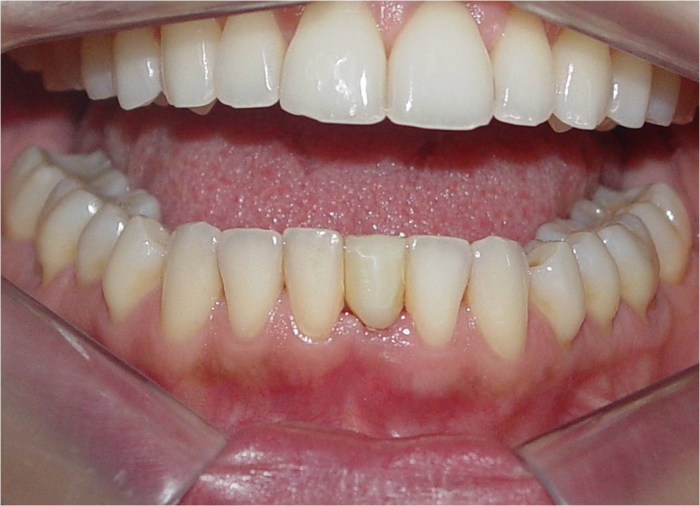

Imagem inicial

Imagem inicial do incisivo central inferior esquerdo fraturado